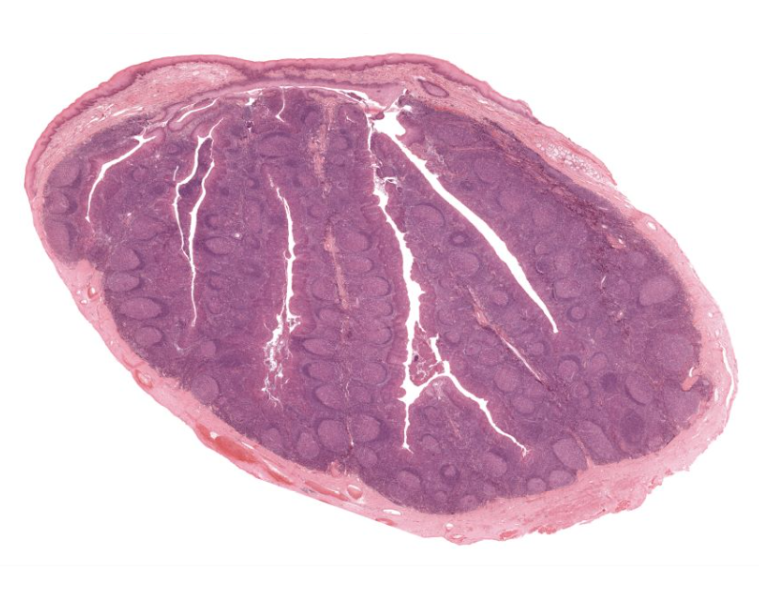

spleen

solid organ

“white” pulp

made up of lymphocytes

lots of basophils

“red” pulp

filters and degrades RBCs